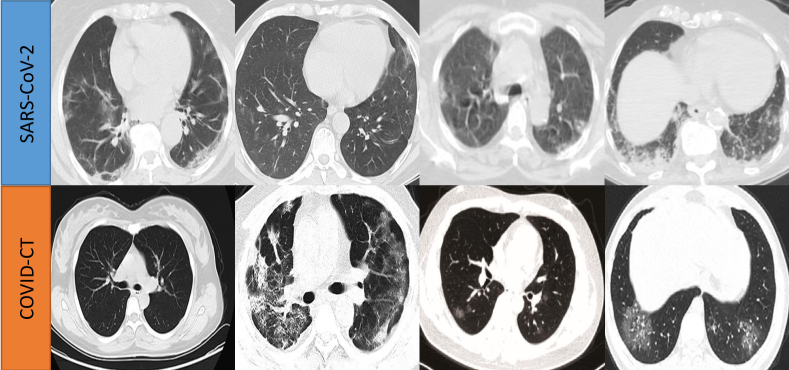

4.1 Datasets and Evaluation Metrics

We adopt two public COVID-19 CT datasets to evaluate our joint learning framework, including SARS-CoV-2 [39] and COVID-CT [40]. To the best of our knowledge, these two datasets are the only relatively large-scale high-quality COVID-19 datasets which are currently publicly available for research. Among the two datasets, the SARS-CoV-2 (denoted as Site A) consists of 2482 CT images from 120 patients, in which 1252 are positive with COVID-19 and 1230 are non-COVID but with other types of lung disease manifestations. The spatial sizes of these images range from 119×104119104119\times 104 to 416×512416512416\times 512. The COVID-CT dataset (denoted as Site B) includes 349 CT images from 216 patients containing clinical findings of COVID-19 and 397 CT images from 171 patients without COVID-19. Resolutions of these images range from 102×137102137102\times 137 to 1853×1485185314851853\times 1485. For the preprocessing of the two datasets, all images are first resized to 224×224224224224\times 224 in axial plane, and then normalized into zero mean and unit variance for intensity values along channel dimension.